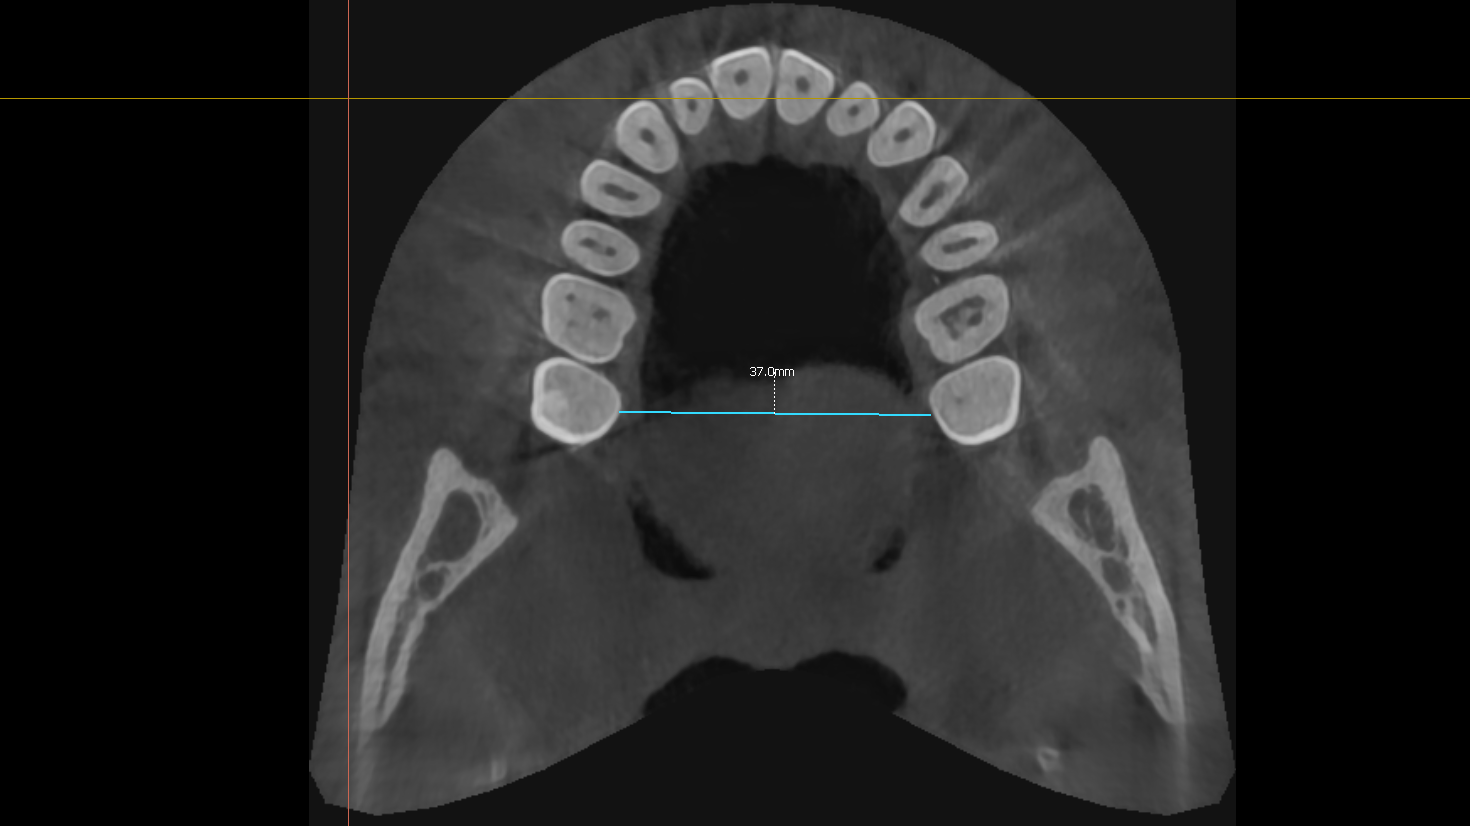

my upper palate is 37mm, is it narrow?

Should I wear marpe or something like that?